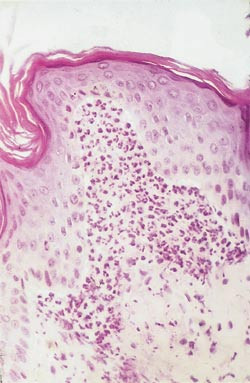

De typiske histopatologiske funn ses best ved ferske, prevesikuløse lesjoner: akkumulering av nøytrofile granulocytter og enkelte eosinofile, som danner papillære mikroabscesser i dermis (fig 3). Slike funn ses også ved lineær IgA-dermatose. Eventuelle bullae er lokalisert subepidermalt og kan likne dem ved bulløs pemfigoid.